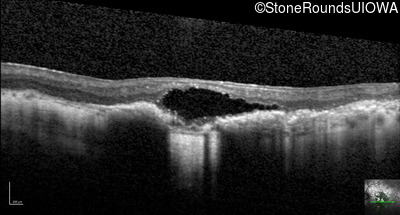

Optical Coherence Tomography - Right - Count Fingers 2'

Exemplar / OCT Stack